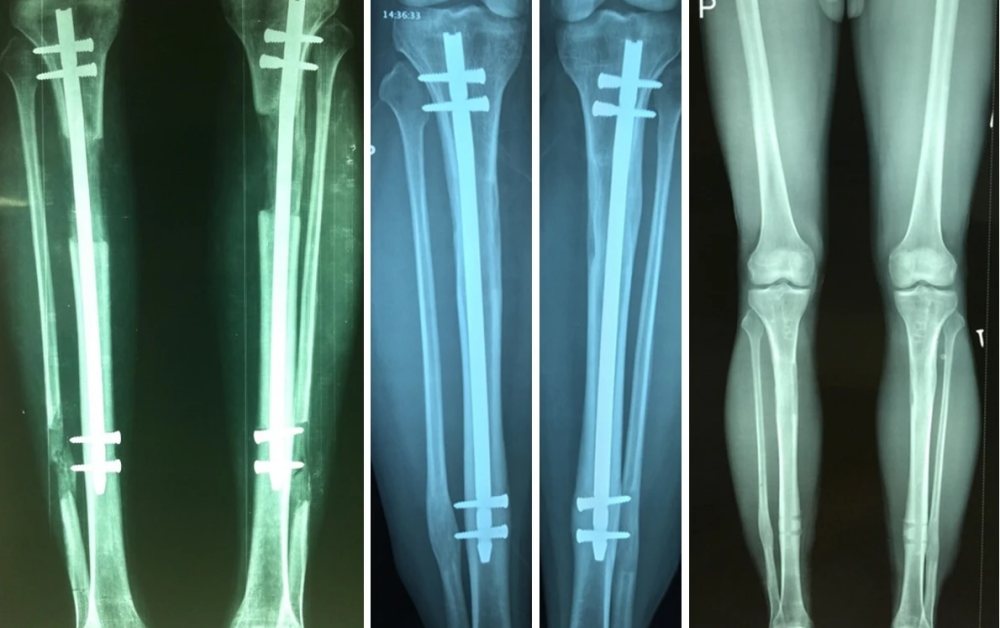

Phim X-quang bệnh nhân sau khi thực hiện kéo dài chân. Ảnh: BSCC.

Phẫu thuật có thể thực hiện ở cẳng chân hoặc xương đùi. Nếu muốn kéo dài hơn, bệnh nhân có thể thực hiện tiếp giai đoạn thứ hai sau khi phần xương đầu tiên đã liền chắc. Xương kéo dài, nếu hồi phục đúng quy trình, có thể vận động bình thường, thậm chí chơi thể thao như đá bóng.